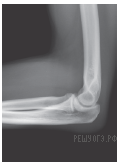

Какой сустав изображен на рентгеновском снимке?

1) голеностопный

2) тазобедренный

3) коленный

4) локтевой

Ответ: